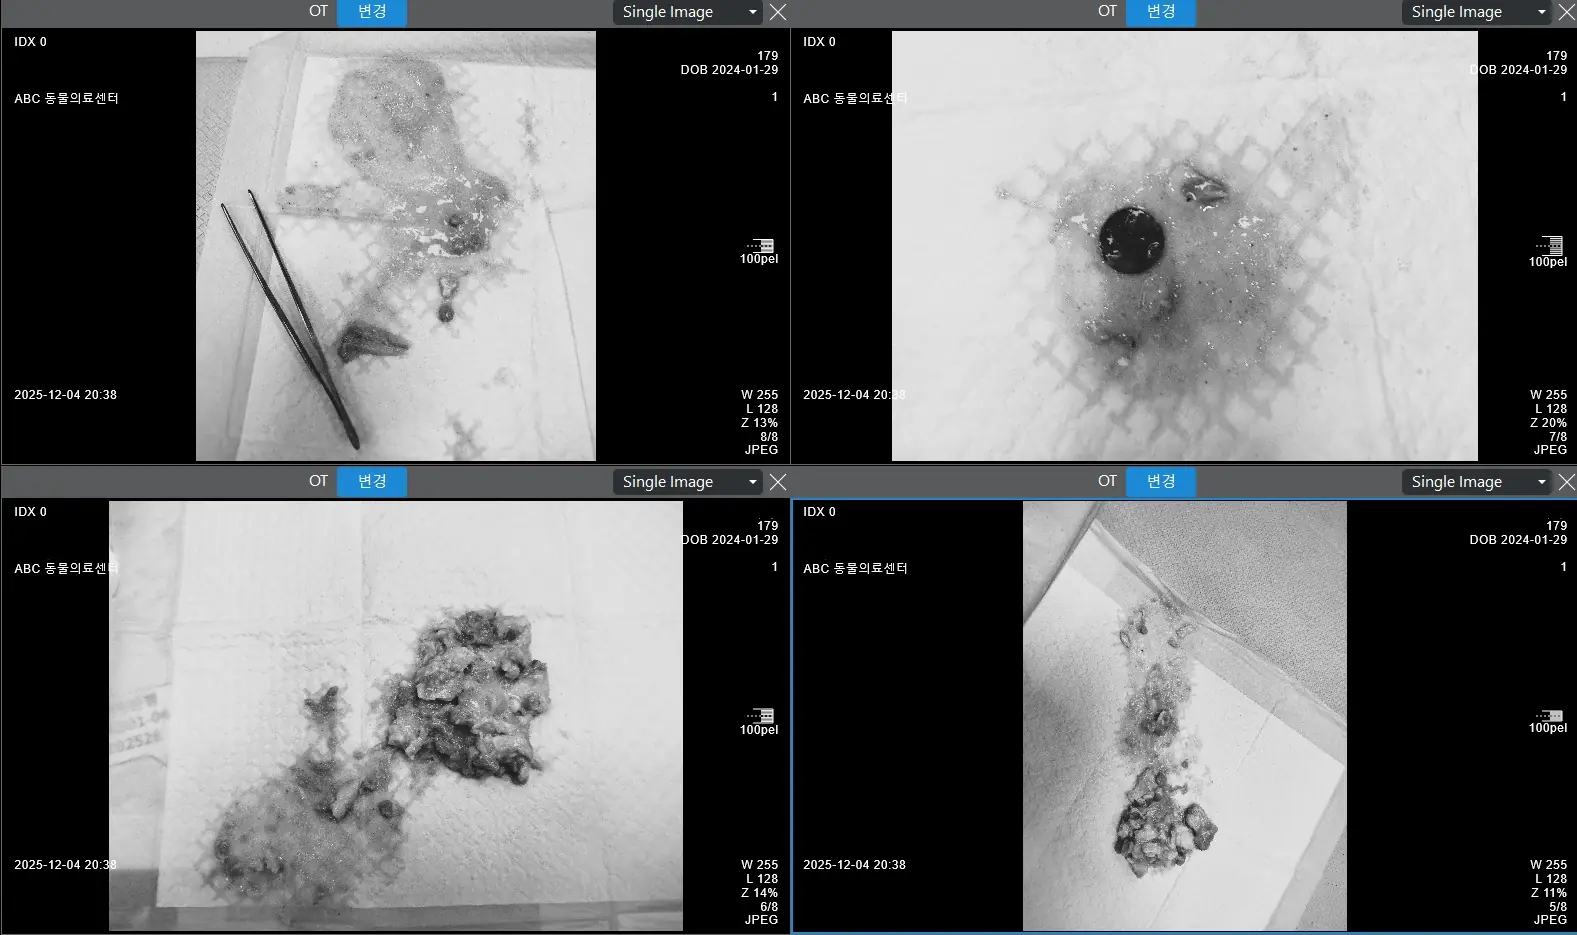

방사선 검사 결과, 강아지 위에 닭뼈와 함께 금속성 이물로 추정되는 원형 물체가 발견되었어요.

즉시 구토 유도 약물을 투여하여 위 내 이물을 배출하는 조치를 취했고, 닭뼈와 10원짜리 동전이 확인되었습니다.